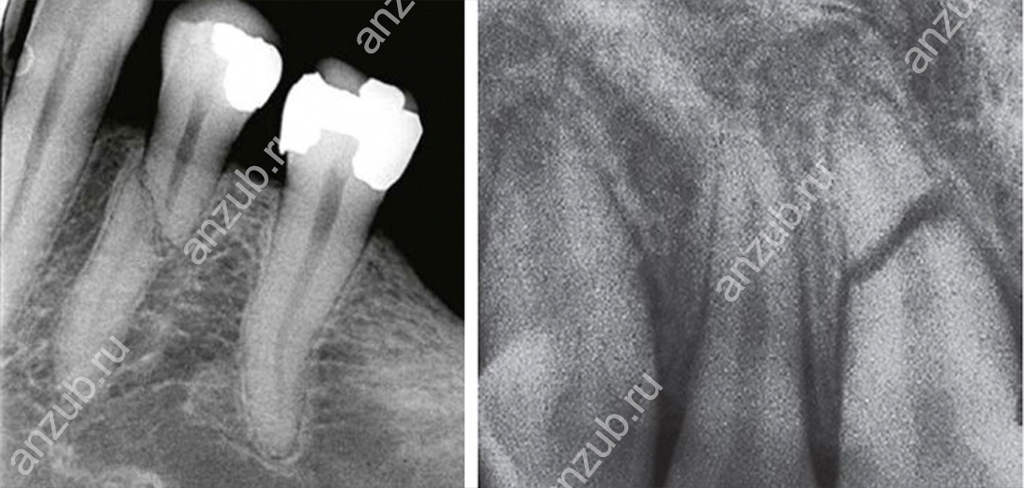

Наиболее информативным методом диагностики будет рентген или, лучше всего, компьютерная томография. С их помощью можно оценить не только место перелома и линию разлома, но и состояние окружающих тканей.

В каждом случае лечение будет подбираться индивидуально. Сегодня даже при малейшей возможности сохранить зуб в хорошей стоматологии врачи ею воспользуются. Методы применяются различные в зависимости от клинической картины. Возможна резекция удаление пульпы и пломбирование каналов, укрепление штифтом, обеспечение неподвижности.

Если же травмы сильные, разломы большие и пролегают вдоль, по диагонали, имеются осколки, то спасти зуб уже, как правило, нельзя. Тогда проводят его удаление и последующее восстановление. Важно только своевременно обратиться к врачу, чтобы исключить осложнения!